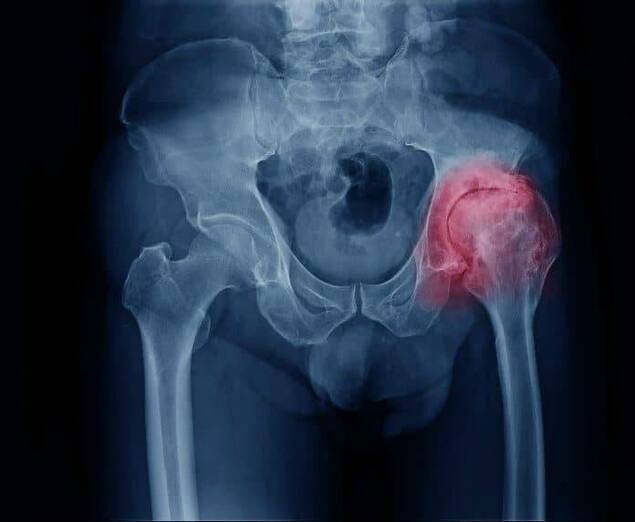

Según datos de la Organización Mundial de la Salud, la artrosis se ubica en el cuarto lugar de las enfermedades que menor calidad de vida otorga a sus pacientes año a año. La artrosis de cadera es uno de los tipos más comunes y afecta el cartílago que recubre la unión de los huesos de la pelvis y el fémur.

El síntoma fundamental que produce la artrosis de cadera es el dolor, el cual suele localizarse en la zona de la ingle, pudiéndose extender hacia la cara anterior del muslo, rodilla y nalga. El paciente suele presentar rigidez matutina y dificultad para caminar.